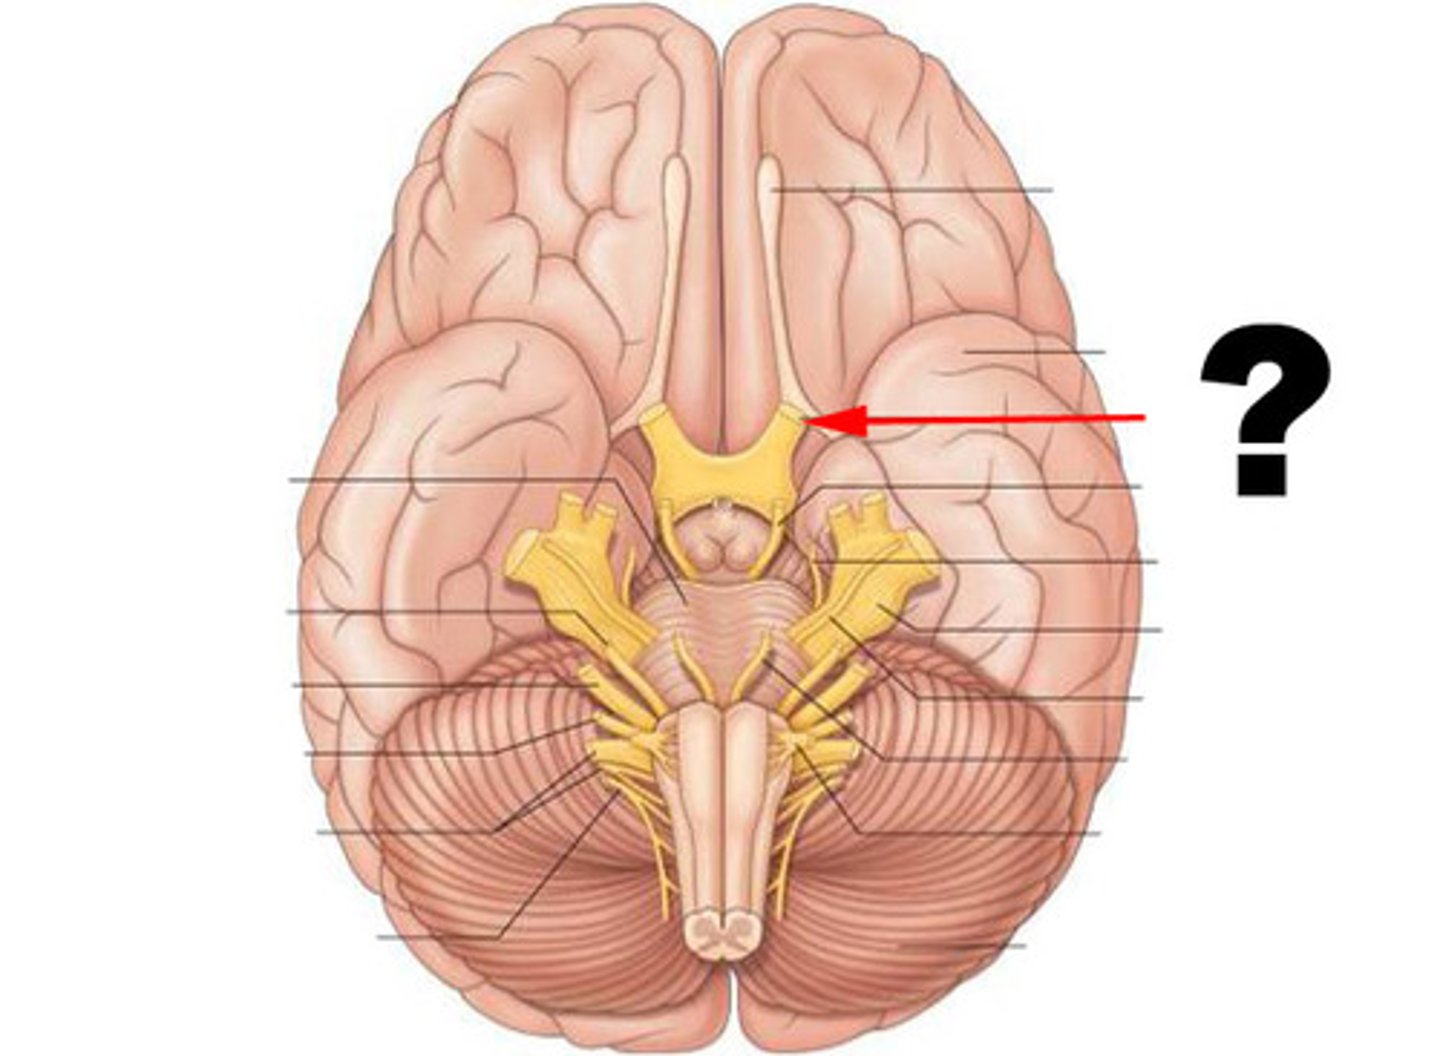

optic nerves (cranial nerve II)

optic chiasma

optic tracts

CNIII (oculomotor nerve)

CNIV (trochlear nerve)

CNVI (abducens nerve)

infundibulum

pituitary gland

mammillary bodies

pons

medulla oblongata